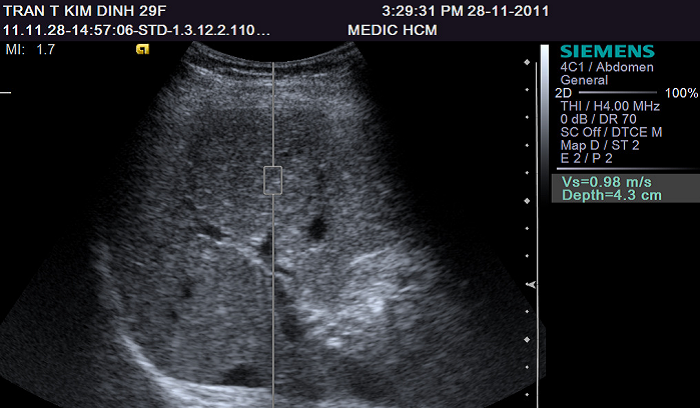

Nang trống âm là một trong các loại u nang buồng trứng, là hiện tượng một vùng hoặc một khối nào đó dội lại tiếng vang trong quá trình siêu âm. Chính vì vậy mà loại nang này được gọi là trống âm hoặc echo. Echo cũng có nghĩa là âm thanh. Như vậy, nang trống âm buồng trứng chính là hiện tượng âm thanh vang lại khi tiến hành siêu âm tại buồng trứng.

Nang trống âm được phát hiện khi siêu âm

Như vậy, có nghĩa là nang trống âm buồng trứng là dạng u nang lành tính. Khi mắc nang trống âm buồng trứng, người bệnh sẽ rất khó để phát hiện ra sự xuất hiện của nó. Thông thường, chỉ khi siêu âm, mới nhận thấy loại nang này.